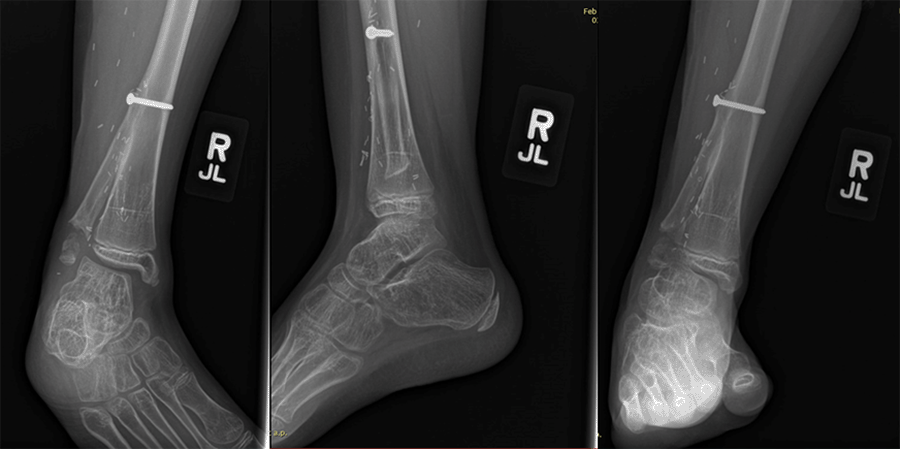

A five-year-old female with no significant past medical history presented with a two-month history of right leg pain without an antecedent traumatic event. On exam, she had a mass over the lateral malleolus on the right. MRI was obtained, which demonstrated a destructive bone lesion measuring 3 × 2 × 14 cm of the distal fibula. She underwent neoadjuvant chemotherapy after a bone biopsy revealed an Ewing sarcoma. Following chemotherapy, her sarcoma was reimaged and found to have decreased in size to 2 × 1 × 11 cm. She was subsequently taken to the operating room and underwent resection of her sarcoma, followed by ipsilateral free vascular transfer of the proximal fibula and epiphyseal plate using the peroneal artery as a pedicle. She is currently 33 months postoperative and is weight-bearing as tolerated to the right lower extremity. She has minimal pain or deformity of the ankle. She has minor hindfoot varus and dynamic supination with gait. She is ambulating independently and is using a lateral heel post to assist with foot position (Figure 1). MRI and plain radiographs were taken at 33 months postoperatively and demonstrated the stable position of the graft with evidence of physeal/epiphyseal remodeling (Figure 2).

Figure 2. Postoperative Radiographs at 33 Months. Published With Permission

Images demonstrate good alignment of flap and stable ankle and physeal/epiphyseal remodeling.